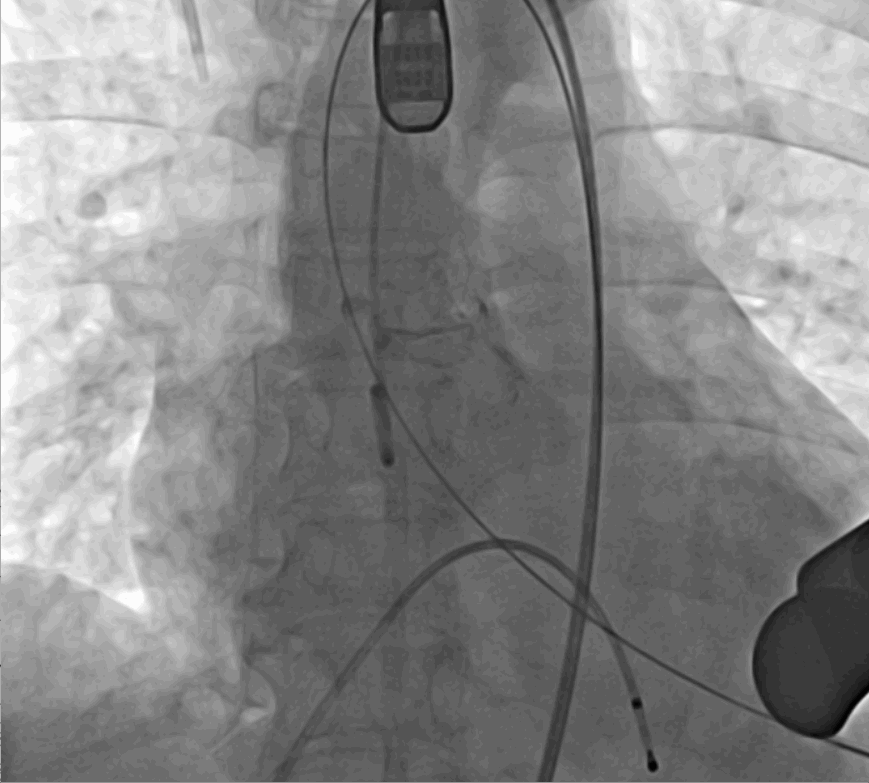

手術(shù)采用經(jīng)心尖入路,對(duì)患者進(jìn)行全麻后,在左側(cè)心尖處做3-4cm微創(chuàng)手術(shù)切口,在DSA及超聲引導(dǎo)下手術(shù)順利完成。從導(dǎo)入器械到完成瓣膜置入,僅耗時(shí)約10分鐘。術(shù)后即刻主動(dòng)脈瓣返流程度由術(shù)前大量返流轉(zhuǎn)為消失,患者于導(dǎo)管室拔除氣管插管,次日由ICU轉(zhuǎn)入普通病房。

術(shù)中釋放定位鍵后DSA影像圖

術(shù)中瓣膜釋放過(guò)程